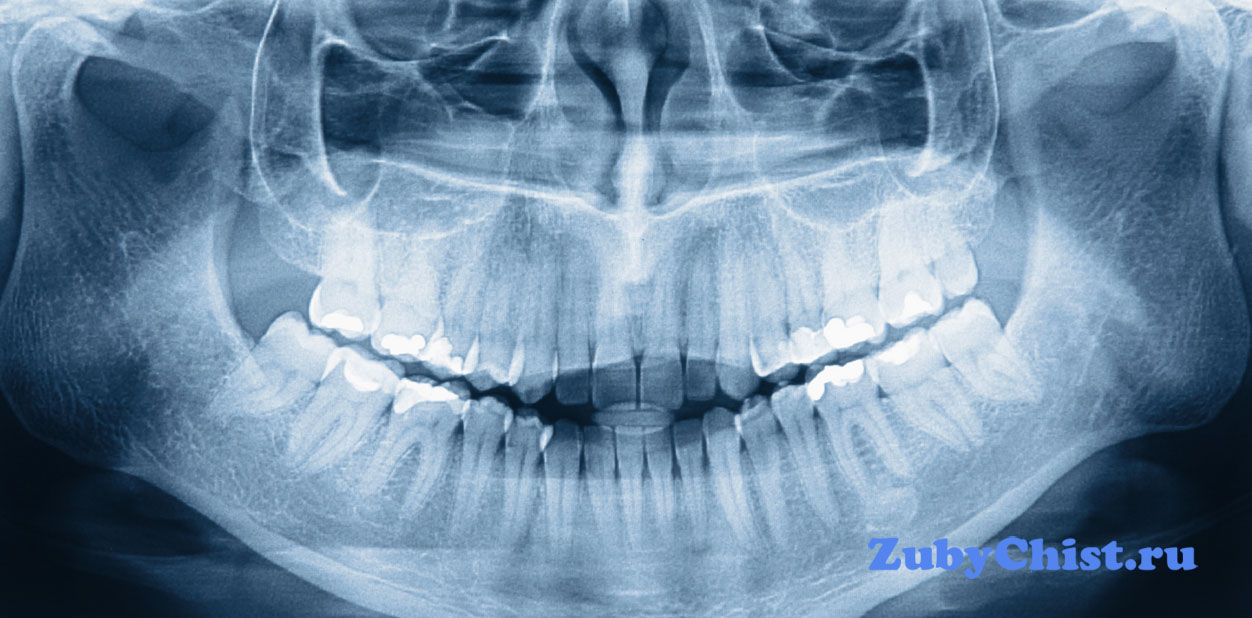

Рентгеновские снимки зубов нужны практически в каждом случае лечения. На основе таких снимков врач может сформировать мнение по поводу состояния тканей, контуров зубной полости. Также стоматолог часто интересуется состоянием каналов в корне зуба, их тоже увидеть можно исключительно на снимке. Современное оборудование позволяет достаточно четко рассмотреть каждый отдельный канал. Если лечение занимает длительный период, не один месяц, то требуется делать несколько снимков. Так, рассматривая, врач сможет увидеть идет ли прогресс в лечении и когда оно закончиться.

Снимок молочных зубов у детей удобно делать на радиовизиографе. С его помощью можно менять контраст в удобную для врача сторону, увеличивать или уменьшать изображение, менять пространственную ориентацию. Можно даже сохранить получившуюся картинку или сразу же распечатать на принтере. 3d снимок зубов позволяет рассмотреть челюсть со всех сторону, увидеть все изъяны корневой системы, подобрать оптимальную точку начала операции. Точность диагностики значительно выше, в значительном числе случаев нужда в классической диагностике отпадает – все видно на мониторе.

Сформулируем основные позитивные моменты, которые дает панорамный снимок зубов:

- Более крупное изображение, которое масштабируется при желании;

- Минимальное облучение радиоактивными лучами;

- Время от снимка до получения фотографии минимально и гораздо меньше, чем при аналоговом рентгене;

- Лучше диагностика.